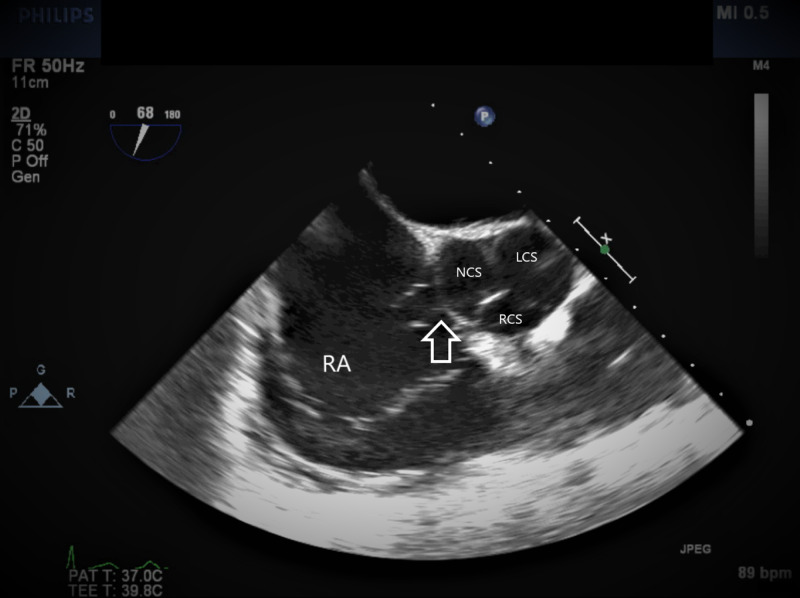

Figure 1. TEE image at mid-esophageal aortic valve short axis view.

The arrow showing SVA arising from the noncoronary sinus.

TEE, transesophageal echocardiogram; SVA, sinus of Valsalva aneurysm; RA, right atrium; NCS, noncoronary sinus; LCS, left coronary sinus; RCS, right coronary sinus.